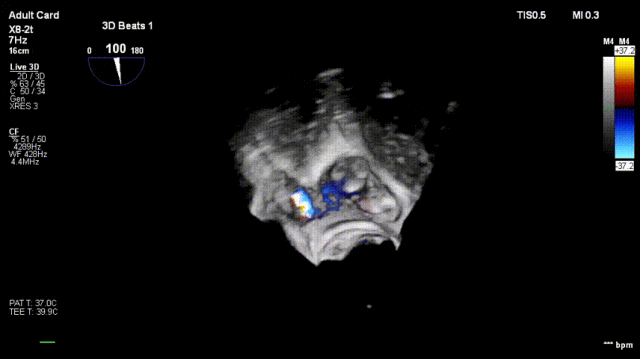

4. The same procedure is performed for the second clip; the clip morphology is stable under ultrasound

Surgical Outcome Assessment

Regurgitation assessment: Regurgitation severity reduced from preoperative 5+ to 1+.

Annuloplasty effect: The tricuspid annulus area decreased from 13 cm² preoperatively to 7 cm².